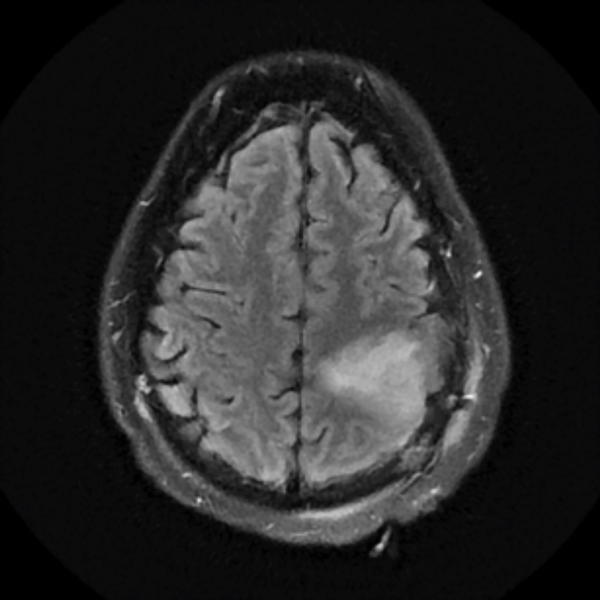

December 2019

Treatment with chemotherapy and radiation under the care of Dr. Grewal resulted in a durable response of the tumor as evident in the post-treatment images.

Neurocognitive assessment by NSPC neuropsychologist Gad Klein, Ph.D., was incorporated into the patient’s care. One month following the initiation of chemotherapy, the patient experienced a marked improvement in seizure frequency, and two months later, he became completely seizure-free. He has now been tapered off seizure medications.

The patient has returned to work with a resolution of cognitive impairment, has no neurological impairment, and the tumor continues to shrink on each serial MRI.